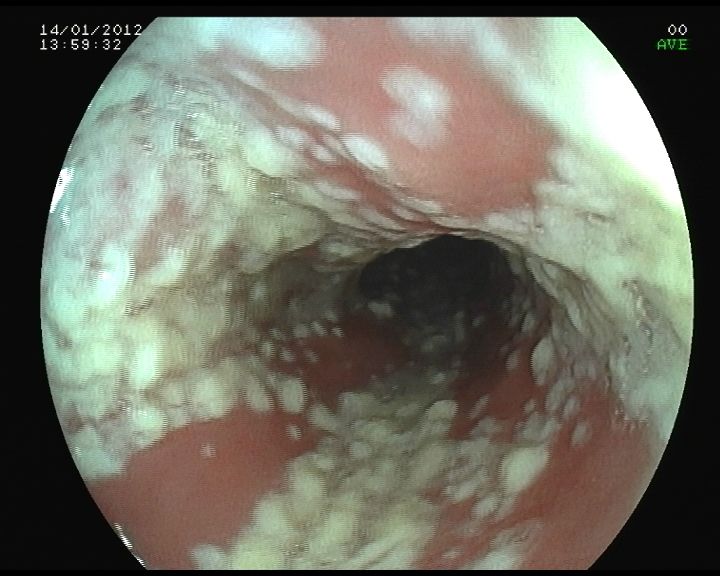

1. Esofagica